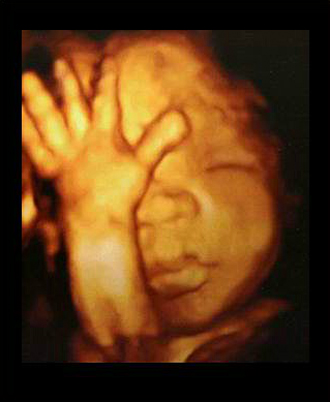

- 4차원 후기 정밀 초음파 (26~28주)

- 필수 검사

- 산전진찰 및 복부 초음파 (1회/2주)

- 막달 산모 종합 검사 (35~36주)

- 태동검사 (34~36주)